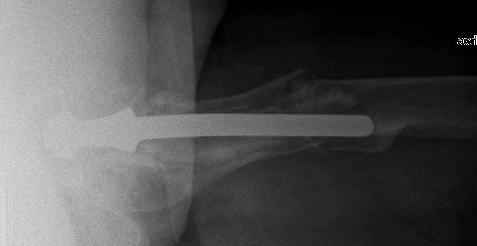

Спасибо за обсуждение. После нескольких дней тракции аппаратом сделали. Попытка закрытой репозиции не удалась из-за смещения по ширине, мешали фрагменты цемента. После их удаления репозиция получилась. Еще убрали немного цемента с ножки по латерльной стороне, чтобы обнажить 40-50 мм ее дистальной части, для плотной посадки гвоздя. Дальнейшее введение гвоздя было несложным. Протез показался нам стабильным в проксимальной части как латерально, так и медиально. Картинки в приложении.

THX for the discussion. After few days of traction by ex-fix the surgery was performed. An attempt of closed nailing was unsuccesful because of fragment translation, which was blocked by cement fragments. After removal of broken cement pieces reduction was reached "automagically". Also some cement from lateral part was removed by

chisel to expose distal 40-50 mm of the stem to allow tight fit of the nail. Further fixation by the nail was pretty easy and straightforward. Images attached. The stem looked stable in its proximal part both laterally and medially. Comments/critics are welcome.

I would like to ask one little question, you said 'tight fit of the nail' to the femoral stem, since all the rotational stability of the system (distal fragment with nail and locking screws) comes from that point, is it reliable?.

The nail tip is jammed. Since it is conical, it can only be jammed more with axial load.

I'd say yes because we use same 6 mm screws for femoral nailing and allow immediate weight-bearing regardless of fracture pattern.